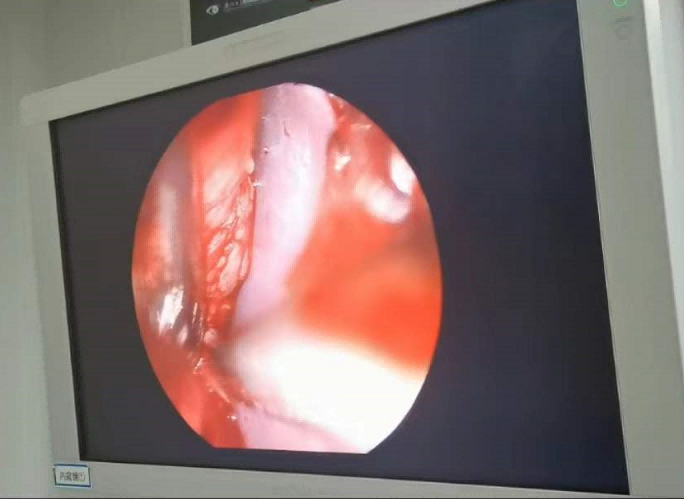

送到廈門眼科中心的時候,林老師受傷的左眼還在流血。眼整形科的鄧?yán)っ鞲敝魅吾t(yī)師緊急為他安排了“內(nèi)鏡下眶骨折修補(bǔ)+鈦網(wǎng)鈦釘植入術(shù)”。

圖為:內(nèi)鏡下眼眶骨折修補(bǔ)術(shù)

手術(shù)過程中林老師還出現(xiàn)了驚險的眼球后大出血,還好鄧?yán)っ饔诰o急之中穩(wěn)住了病情,并順利完成了手術(shù)。術(shù)后第二天,林老師的術(shù)后反應(yīng)就很輕,恢復(fù)良好,他一邊感謝著鄧?yán)っ鞯?ldquo;救命之恩”,一邊自嘲著自己示范了個“反面教材”。